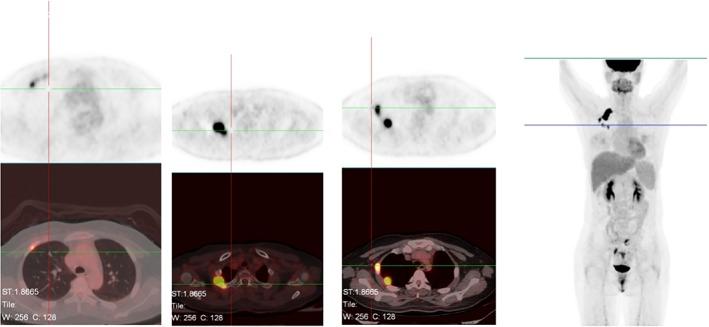

Common gene fusion of the ALK gene is fusion of the ALK tyrosine kinase area and the 5'end of EML4. Seventeen EML4-ALK fusion variants have been reported. Herein, we report a novel EML4-ALK variant detected by next-generation sequencing in a 36-year-old female lung adenocarcinoma patient who experienced disease progression after six months of alectinib treatment. Second generation sequencing revealed an EML4-ALK fusion variant in which intron 19 of EML4 was fused to exon 20 of ALK. This is the first case of EML4-ALK (E19: A20) fusion to be reported. Alectinib may show unsatisfactory therapeutic effects for this kind of ALK fusion.

ALK 基因的常见基因融合是 ALK 酪氨酸激酶区域和 EML4 的 5'端融合。已经报道了十七种 EML4-ALK 融合变体。在此,我们报告了一例通过下一代测序检测到的新的 EML4-ALK 变体,该变体存在于一名 36 岁的女性肺腺癌患者中,该患者在接受阿来替尼治疗六个月后出现疾病进展。二代测序显示 EML4 的内含子 19 与 ALK 的外显子 20 融合。这是首例报道的 EML4-ALK(E19:A20)融合。阿来替尼可能对这种 ALK 融合显示出不理想的治疗效果。